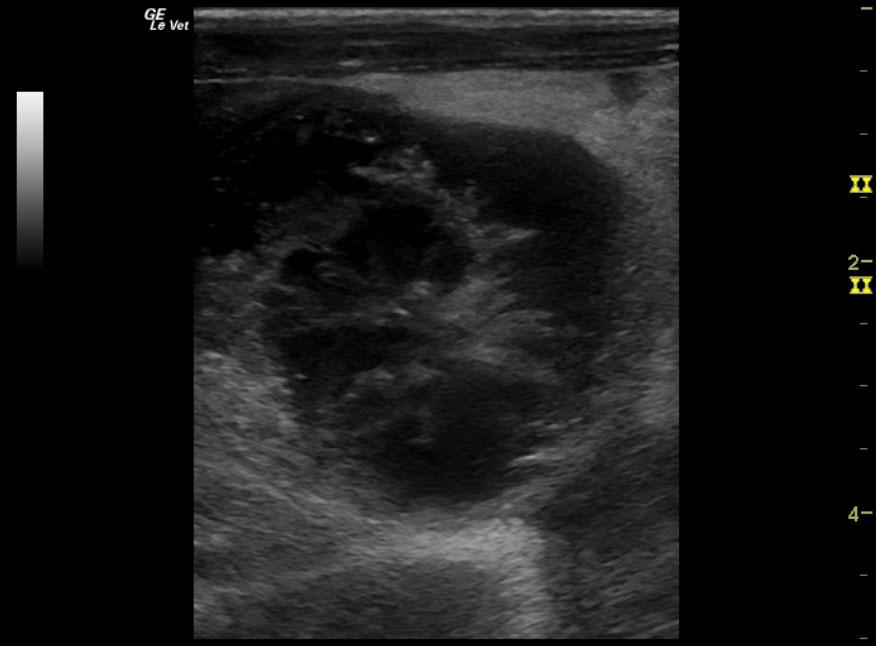

A 12-year-old NM Maltese with a history of pituitary dependent hyperadrenocorticism that was being treated with Lysodren was presented for vomiting, anorexia and not doing well over a 2-day period. Urinalysis showed an inappropriate SG (1.018), proteinuria, and bilirubinuria. Abnormalities on CBC and serum biochemistry were leukocytosis, severely elevated ALT and severely elevated ALP activity, hypoalbuminemia, bilirubinemia, and azotemia. The patient was treated with antibiotics, to which there was some response.